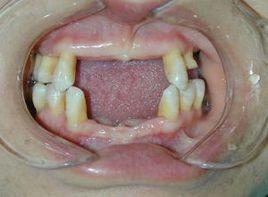

先天缺牙可發生在乳牙列,也可發生在恆牙列。乳牙列缺失情況較少發生。一般為上頜乳側切牙,下頜乳側切牙和乳尖牙。恆牙列最常缺失的牙齒為:下頜第二雙尖牙,上頜側切牙,第三磨牙,上頜第二雙尖牙,下頜側切牙和切牙。缺失數目最常見為2顆,其次是1顆,缺失5顆以上少見。缺牙少的沒有明顯的全身意義。相反,缺牙數目多時,應檢查全身有無其他方面的異常,如皮膚,毛髮等。常是外胚葉發育不全綜合徵的一種表現,是一種全身性的先天畸形。患兒先天性缺失乳牙和恆牙,並伴皮膚和毛髮的發育異常。是屬於退化性的發育畸形,多數為男性。根據患兒是否出汗,臨床上分成有汗型外胚葉發育不全和無汗型外胚葉發育不全兩種類型。

全身皮膚汗腺缺乏,故患兒不出汗或很少出汗,體溫調節障礙,畏熱,皮脂腺,毛囊和汗毛全無或稀少,以致皮膚乾燥,粗糙。頭髮,眉毛稀疏,細又黃,似胎兒毛,鼻樑下陷,沒有鼻毛。因此不能過濾空氣中的灰塵;鼻腔黏膜乾燥,並容易引起慢性萎縮性鼻炎。口腔內由於牙齒大多缺失,僅有的幾顆牙,殘存的牙距離稀疏,牙形小,呈園錐狀,口唇突出。